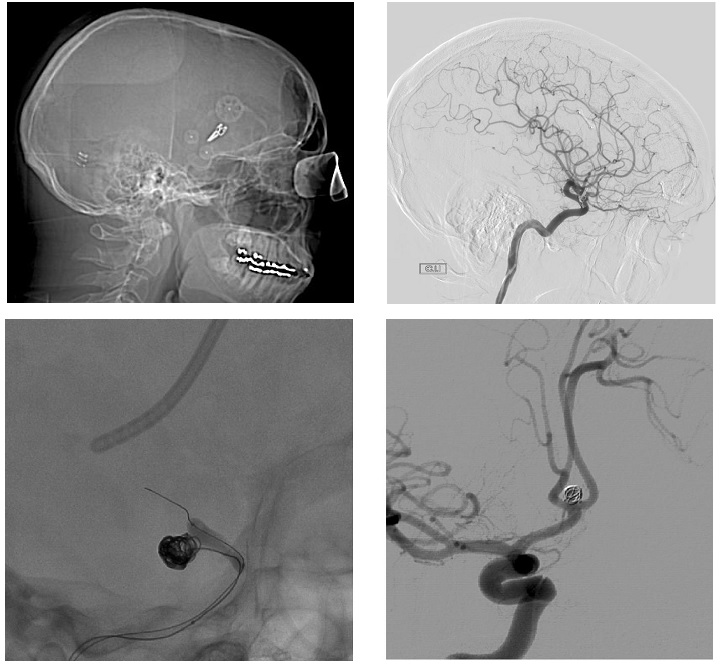

Computed tomography (CT) is the most sensitive test in the diagnosis of SAH and should always be practiced as soon as possible after the clinical suspicion of SAH. The quantification of the blood supply in the subarachnoid space is very difficult to determine. The scale most used today is Fisher's, although others have been proposed that take into account the volume of intraventricular bleeding. Clinically, the Hunt and Hess Scale is also used. However, the standard test for the diagnosis of aneurysms responsible for SAH is still cerebral angiography (Figure 1) to rule out the presence of underlying vascular pathology.

Figure 1 Images of SAH in CT (Above) and cerebral Arteriography with aneurysm of middle cerebral artery (Down).

When comparing both types of treatment (Figure 2), no statistically significant differences were found in the mean global hospital stay (clipados = 32 days, embolized = 28 days, p = 0.29); the number of admissions made by each patient; the number of patients who needed new admission (clipping = 59.41%; embolized = 65.38%, p = 0.37); the average stay in ICU (clipados = 8 days; embolized = 9 days, p = 0.47); the time elapsed since the SAH and the treatment applied (clipping = 6 days; embolized = 4 days, p = 0.13); the average postoperative stay (clipping = 23 days, embolization = 23 days, p = 0.98) and morbidity that developed after both surgical or vascular procedures (clipping = 5.76%; embolization = 1.13%, p = 0, 62).

Figure 2 Surgical treatment in upper images and endovascular embolization in lower images.